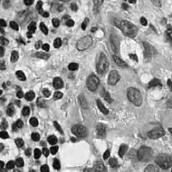

Pathology slides contain abundant phenotypic information, and are widely used to study the manifestations of disease by analyzing cells or tissues under the microscope by pathologists [1]. Nuclei segmentation is a crucial step in pathology image analysis. The shape, size, density, and other indicators of the nucleus are related to the diagnosis and treatment of cancer [2, 3]. Different staining methods are used to increase the contrast between the different structures for their visual examination, where the most commonly used staining method for nuclei analysis is hematoxylin-eosin (H&E) staining, in which nuclei are stained blue-purple by hematoxylin (H-component), and cytoplasm and stromal matrix are stained red-pink by eosin (E-component) [4, 5], as shown in Fig. 1. Besides, with the advent of dedicated scanners, slices can be easily converted to digital pathology images, which are convenient to store on computers for further processing and analysis. Therefore, the wide availability of digital H&E stained pathology images greatly facilitates researchers in developing and validating advanced automatic pathological image analysis methods with nuclei segmentation.

Point annotation can be viewed as the most efficient manner for annotation, gaining increasing attention in cell/nuclei segmentation. Existing methods [23, 24, 25, 26] mainly encode the point annotation into coarse pixel-level labels, such as point distance maps [23], Voronoi labels [24], cluster labels [25], and pseudo edge maps [26]. As shown in Fig. 1, these methods typically inject the shape and texture prior knowledge of nuclei into coarse pixel-level label. For example, the points are assumed to be around the center and the nuclei shapes are nearly convex. Despite drastically reducing the annotation cost and alleviating the data-imbalance problem of point annotation, these methods still suffer from incomplete coarse labels and inaccurate boundary information, as illustrated in Fig. 1. Various methods have been proposed to eliminate the distraction induced by the coarse labels, which can be categorized into two classes: 1) multi-stage optimization to refine the segmentation in a bootstrapping way [23, 27, 24]; 2) adding additional constraints based on the local contrast between nuclei and their surrounding cytoplasm [25, 26]. However, the additional constraints could introduce inaccurate supervision, and a multi-stage learning strategy may suffer from error accumulation (i.e., the global optimum cannot be guaranteed).

In practice, directly using point annotation for the nuclei segmentation could suffer from the data-imbalance problem due to insufficient supervision information. To alleviate this issue, we adopt the Voronoi diagram [24] and the -means clustering method [25] to generate Voronoi label and cluster label, respectively. Specifically, for Voronoi labels, as shown in Fig. 1, the image is divided into convex polygons based on the point annotations with the assumptions that the point labels are at the nuclei centers and nuclear shapes are convex (even though these assumptions are not necessarily valid). For cluster labels, as shown in Fig. 1, we utilize the -means to obtain more supervision information of nuclei boundary and shape as follows. First, we calculate the distance maps from the point labels by performing distance transform between each pair of points. Second, the distance maps are combined with the original H&E stained images to conduct the -means clustering to divide all pixels into clusters: nuclei, background, and ignored area. The clusters that have maximum and minimum overlap with the point annotations are labeled as nuclei and background, respectively. The remaining one is the ignored class. The introduction of an ignored area allows pixels that cannot be easily determined as nuclei or background with certainty not be forced into either class, ensuring that the clustering can assign correct pixel labels as much as possible [27]. Third, several morphological operations are adopted to refine the cluster label, including connected domain labeling, scattered region removing, morphological opening operation, and binary hole filling.

As shown in Fig. 1, although part of the color information is lost in the obtained H-component image, the color contrast between the nuclear and non-nuclear regions is enhanced.

where and denote the Voronoi label and cluster label of nuclei at the -th pixel, respectively; denotes the prediction of the segmentation network with H-component as input; and (i.e., or ) is the set of non-ignored pixels. As illustrated in Fig. 1, the Voronoi label is used to supervise the network to separate overlapping nuclei, while the cluster label could provide coarse shape and boundary information for nuclei segmentation. In the following, we elaborate the co-training strategy to further provide supervision to the ignored area of the coarse cluster labels, denoted with the blue color in Fig. 1.

where is the -th pixel of the pseudo label, is the set of all pixels, and denotes the predictions of with respect to the H-component . With the training set split into two non-overlapping subsets and , two segmentation networks are trained with the coarse labels (i.e., the Voronoi and cluster labels) by and , respectively, the two networks could transfer knowledge to each other with their respective pseudo labels, so as to compensate for the missing supervision information. However, the segmentation performance may still suffer from the inaccurate cluster label, as shown in Fig. 1. Hence, our next step is to explore an auxiliary colorization task that transforms H-component images back into the original H&E stained images from which more precise nuclei boundaries can be obtained.

To investigate the impact of the proposed co-training and colorization methods, we validate the effectiveness of each module on the MoNuSeg dataset. Considering that Voronoi labels provide more shape supervision information than point annotation, we regard the model that jointly uses the point annotation and the Voronoi label as the baseline, and mainly evaluate the improvement of each module upon this baseline in Table III. Model A utilizes only point annotation and Voronoi labels with cross-entropy loss. For a fair comparison with co-training, we employ two separate models which have the same architectures for co-training and average the predictions of the two models in inference. Model B further adopts the cluster label. It can be seen that the cluster loss is beneficial in segmenting overlapping nuclei, improving the from 60.20% to 72.48% and the AJI from 43.01% to 51.77%, which indicates that simply using the point annotation and the derived Voronoi labels cannot provide sufficient supervision for the nuclei segmentation due to the lack of boundary and area information. However, the cluster labels generated by the -means algorithm cannot separate close nuclei which would introduce distraction to the training process, as shown in Fig. 1. To address this challenge, Model C utilizes the co-training strategy that the two models facilitate each other in a bootstrapping way to eliminate the distraction brought by the cluster labels. As expected, co-training brings a consistent improvement in all metrics, including an 1.19% increase to AJI. We believe that co-training compensates for the loss of supervision information in the uncertain regions in the cluster label, and the probability map with EMA by another model provides more precise and robust supervision in the nuclei boundary. Visualization of the segmentation results can be found in Fig. 3, and it can be seen that with the co-training strategy, the model can achieve more accurate results, especially in the nuclei boundary area. Model D involves colorization as a proxy task to implicitly learn to be self-aware of the nuclei boundary. Instead of directly coloring the H-component (Fig. 4(a)) to the H&E map (Fig. 4(d)), we use the segmentation probability map (Fig. 4(b)) as the input of the colorization network, which can help us to boost the segmentation accuracy. The experimental result shows that integrating the colorization tasks could not only improve the by 1.54% and AJI by 3.24%, but also promote Acc by 0.18% without dropping F1 score, proving that the colorization task has a significant guiding effect on nuclei segmentation. In Fig. 4(c), the improvement of colorization in the nuclei boundary area can also be observed. In general, the four modules used in our method have complementary advantages. By minimizing the weighted sum of the four losses, the proposed framework can distinguish between nuclear and non-nuclear to the greatest extent.